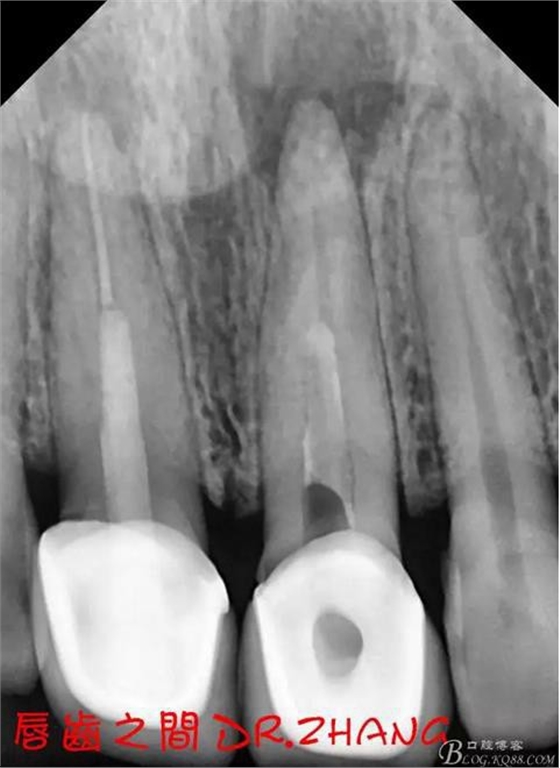

復(fù)診:腫脹明顯消失 患者自訴感覺(jué)良好 溝通后決定拆除11 21兩顆烤瓷冠后重新修復(fù) 去冠器直接去冠 去除11根管內(nèi)的充填物 15#K銼疏通根管 11 21根長(zhǎng)均為16MM平斷面 薩尼S3系統(tǒng)機(jī)擴(kuò)至2S 期間不斷用氯己定和鹽水交替沖洗 吸潮紙尖干燥根管后06 25#試尖

思博安熱牙膠系統(tǒng)根充 燙斷至根尖三分之一處后纖維樁恢復(fù)牙體組織